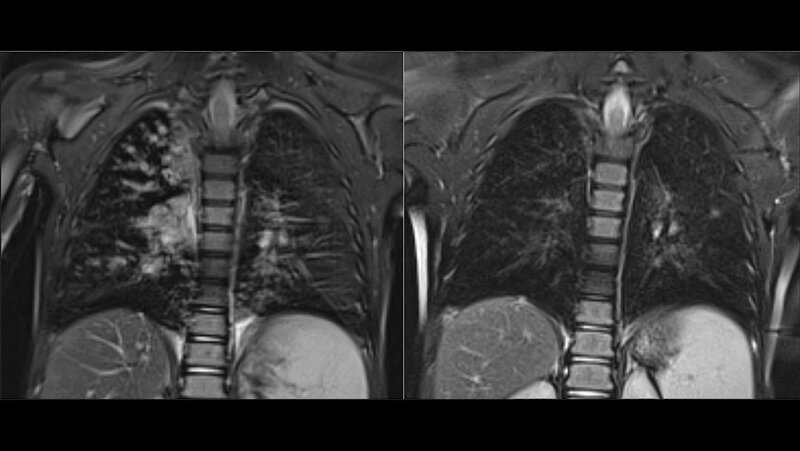

Anhand der Daten von 107 Kindern, die an Mukoviszidose leiden, konnten die Forschenden den deutlichen Nutzen zeigen. Innerhalb eines einjährigen Untersuchungszeitraums der Kinder zeigte sich, dass die Dreifachtherapie nicht nur die Schwere der Symptome reduziert, sondern auch das Voranschreiten der Erkrankung stoppt. Bei den meisten Kindern übertrafen die Werte sogar die der Erwachsenen und sie erlangten eine normale Lungenfunktion.

Momentan wird eine ähnliche Studie für Kinder zwischen zwei und fünf Jahren durchgeführt. Die Hoffnung ist, dass ein früher Start der Behandlung die Entwicklung schwerwiegender Symptome und strukturelle Veränderungen der Lunge verhindern kann. Zudem untersuchen sie, ob sich die Basistherapie der Symptome durch die Dreifachtherapie reduzieren lässt.